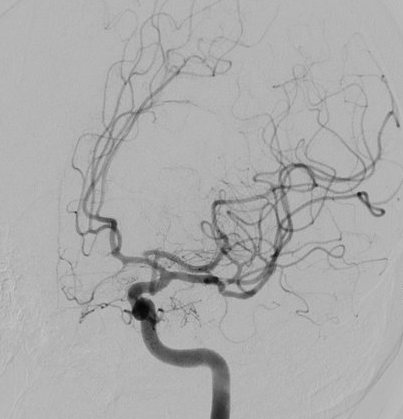

Angiografia cerebrale di controllo post-operatorio